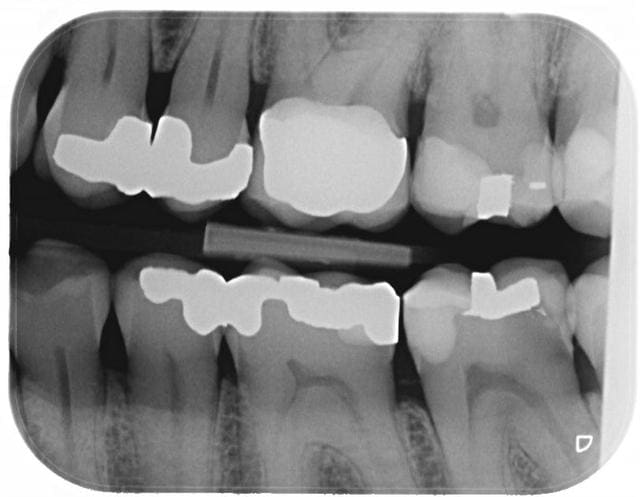

Je compare les btw precedents et tombe sur un hic au niveau de 36 en evolution depuis 2010.

Pour ce que je vois sur les radios, ces soins sont propres, mais pas exceptionnels. Notamment les faces proximales, reconstituées avec des matrices insuffisamment galbées qui produisent un point de contact presque occlusal et qui ne protège pas très bien l'espace inter dentaire en évitant aux aliments de se coincer.

Ceci étant, nous avons tous des patients qui ne passent pas assez les brossettes inter dentaires et déclenchent des caries cervicales incontrôlées.

A stade où nous en sommes, la pulpectomie semble difficile à éviter. Ton patron devrait s'en réjouir, sauf s'il n'est pas payé au pourcentage.

je m'inquiéterais aussi pour la 25.

face distal de 23 également, y a une petite radio clarté.